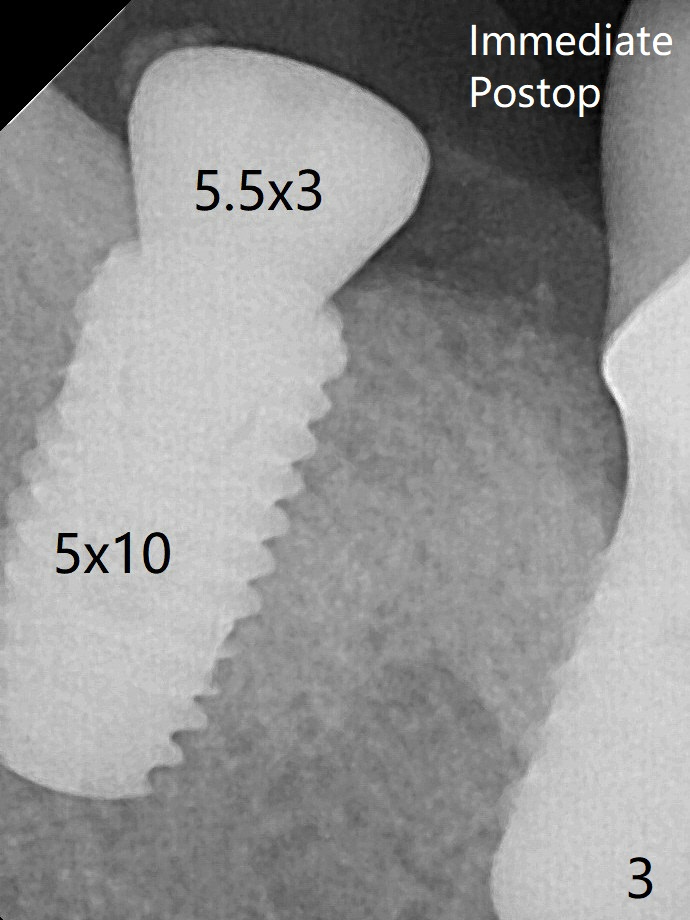

术后2.5月愈合基台脱落,换至小号基台(4x5毫米),仍旧疼痛,休息2分钟,手拧紧,拍摄根尖片,仿佛就位(图四)。准备一周后调换稍微大,例如,4.8毫米基台。